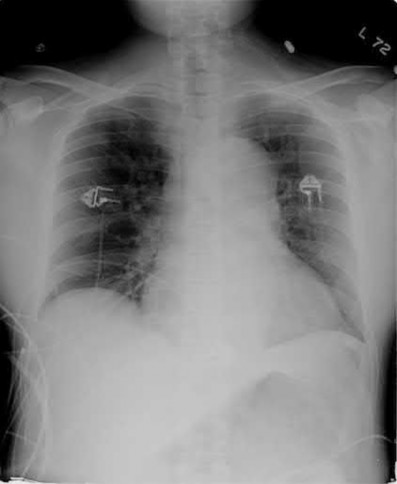

A 62-year-old right-hand-dominant school teacher sustains a mechanical fall at home and presents with right shoulder pain. Plain

radiographs of the right shoulder are pictured in Figures A and B. The patient asks you what she can expect in terms of recovery following this injury. Which of the following is the most appropriate statement?

This patient has a minimally displaced (1-part) proximal humerus fracture involving the humeral neck and greater tuberosity. This injury pattern is most commonly managed nonoperatively with the majority of patients returning to their baseline functional status by 1 year.

Proximal humerus fractures (PHF) can be classified by number of parts (Neer classification), with a part defined as a fracture fragment displaced > 1cm (> 5mm for greater tuberosity) or angulated > 45°. One-part PHF comprise ~80% of all PHF and are treated nonoperatively with a sling and early range of motion (ROM).

Tejwani et al performed a prospective study of 67 patients with 1-part PHF. At 1-year follow up the ASES score and functional status was similar to pre-injury status. However, ROM of the affected shoulder was diminished in both external and internal rotation. Forward flexion was preserved.

Hanson et al prospectively analyzed 160 patients with PHF of all types (1-4 parts and head-splitting) managed nonoperatively. At 1-year follow up, 93% showed solid union. Constant and DASH scores improved steadily over time but were still lower compared to the contralateral extremity. Of employed patients, 97.6% returned to work with a median time off of 10 weeks and no difference between manual and nonmanual workers.

Figures A and B are the AP and axillary radiographs of the right shoulder, respectively, demonstrating a 1-part PHF involving the humeral neck and greater tuberosity.

Answer 1: At 1-year follow up, most patients have restored forward flexion but lack both internal and external rotation compared to the contralateral extremity.

Answer 3: Early ROM exercises starting at 2 weeks post-injury have not been shown to result in fracture displacement. Patients managed with early rehabilitation exhibit high union rates and largely return to baseline functional status.

Answer 4: The vast majority of patients with PHF of all types return to work post-injury.

Answer 5: One-part PHF have an excellent union rate (>90%) and rarely require surgery.